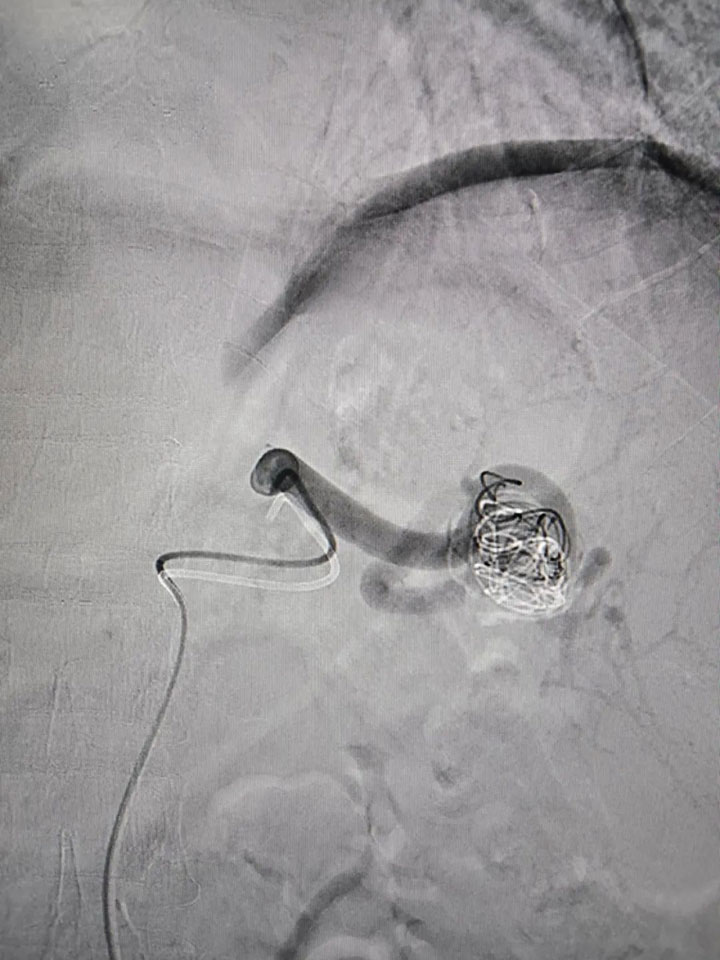

经过完善的术前评估,普外科邀请集团普外医疗中心血管外科桂锐主任、胡玉东主任,仅在股动脉做一2cm小切口,通过一根导丝,精准定位瘤体位置,将弹簧圈置入瘤腔,顺利完成手术。

经过严格的术后管理,患者第二天已经可以下床活动。导丝代替手术刀,无孔不入的介入手术,对比开放手术,不仅定位准确、创伤小、见效快、而且痛苦少、恢复快、并发症少、疗效好,以及简便安全等诸多优点。目前,脾动脉瘤介入治疗(包含脾动脉瘤腔内隔绝术、弹簧栓塞术伴/不伴裸支架辅助等)成为动脉瘤疾病的首选治疗方法。依托集团普外科医疗中心技术优势,广济医院普外科让患者在家门口享受到三级甲等综合性医院的医疗服务,常规开展动脉瘤支架植入,脾动脉栓塞,肝恶性肿瘤化疗栓塞,PTCD,ERCP等肿瘤血管介入手术治疗。